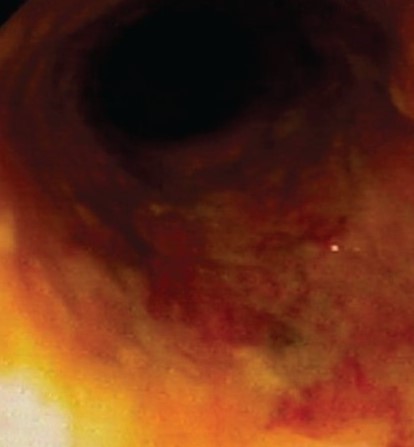

Κολονοσκόπηση. Ευδιάκριτα ευρήματα ισχαιμικής κολίτιδας (Ευγενική παραχώρηση Dr. V. Penopoulos)

Λεπτομέρεια των εκτεταμένων βλαβών στο εγκάρσιο κόλον (Ευγενική παραχώρηση Dr. V. Penopoulos)